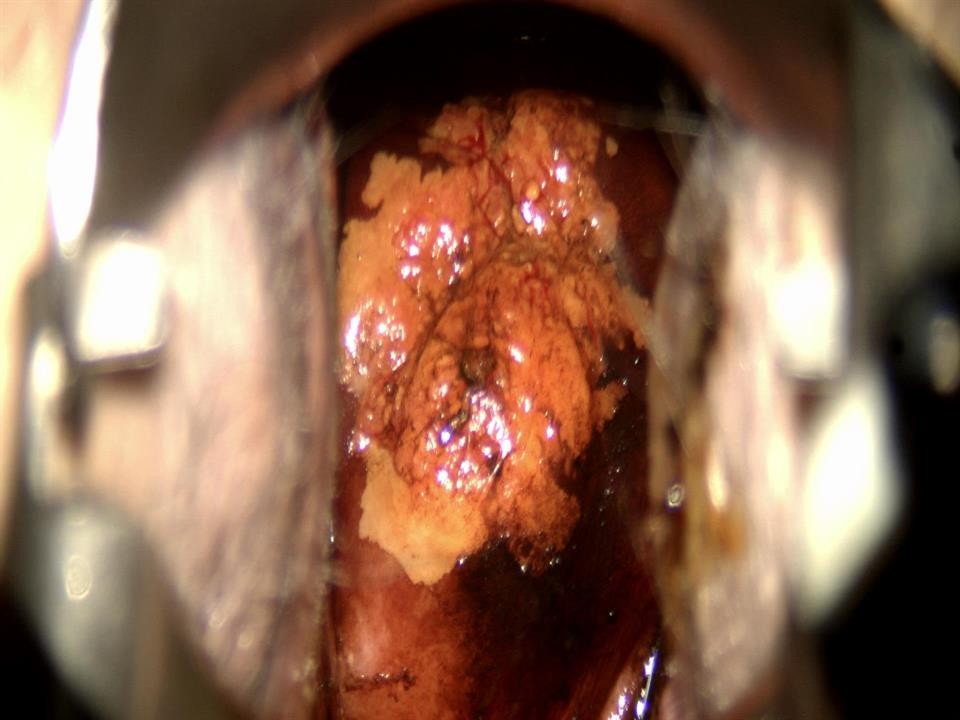

Hình ảnh tổn thương cổ tử cung sau điều trị